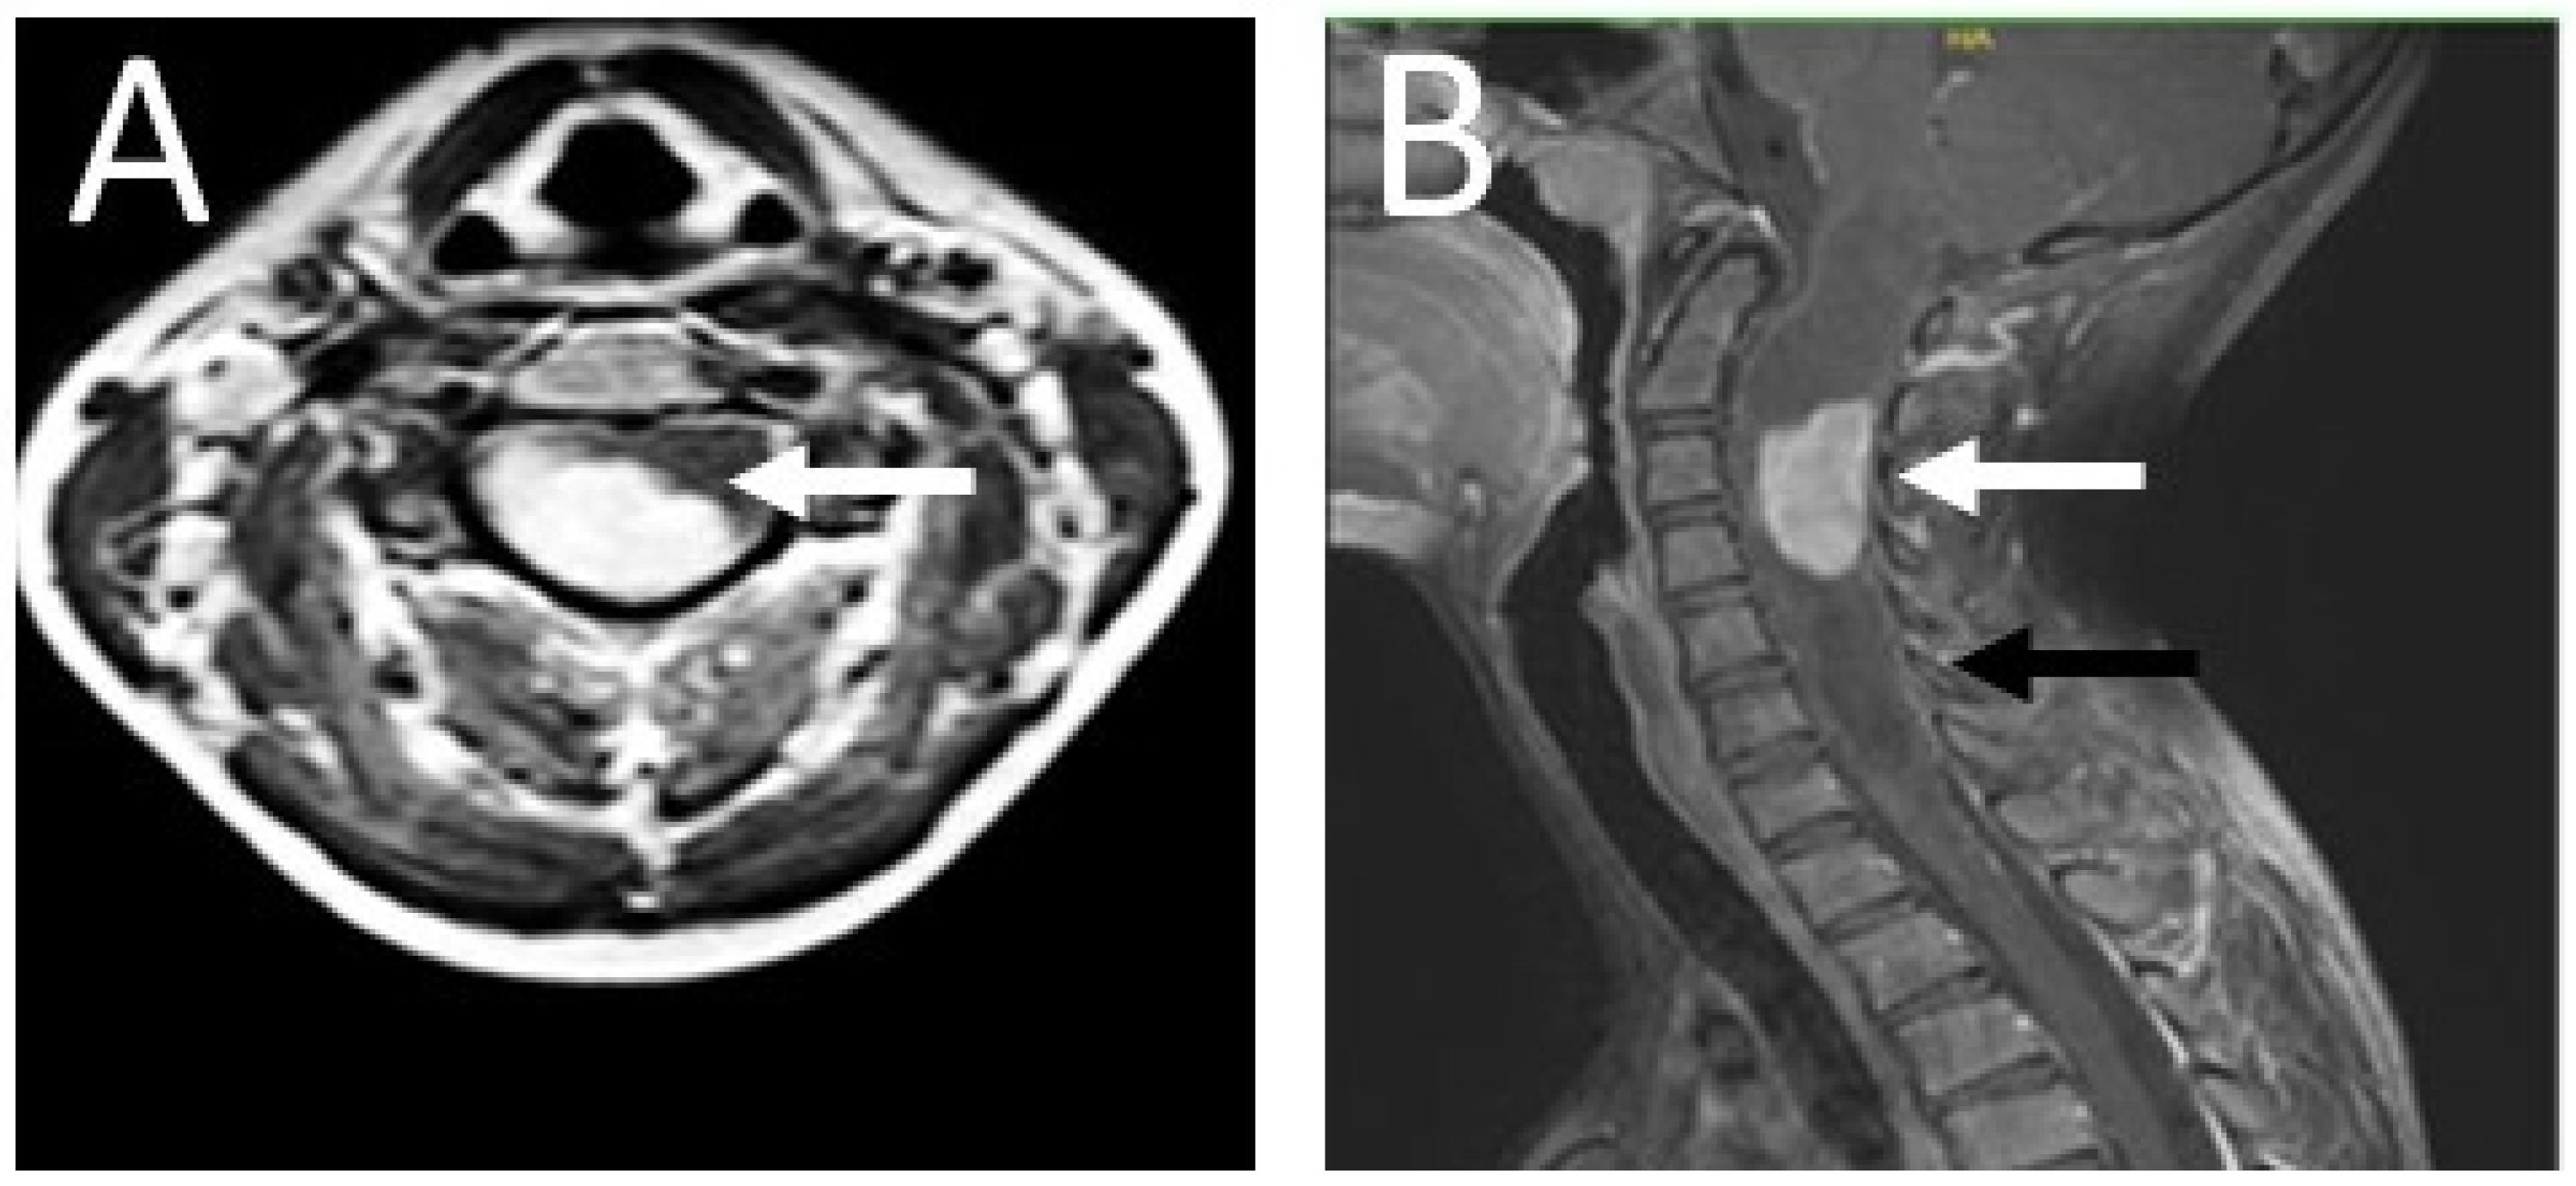

2. Case Presentation